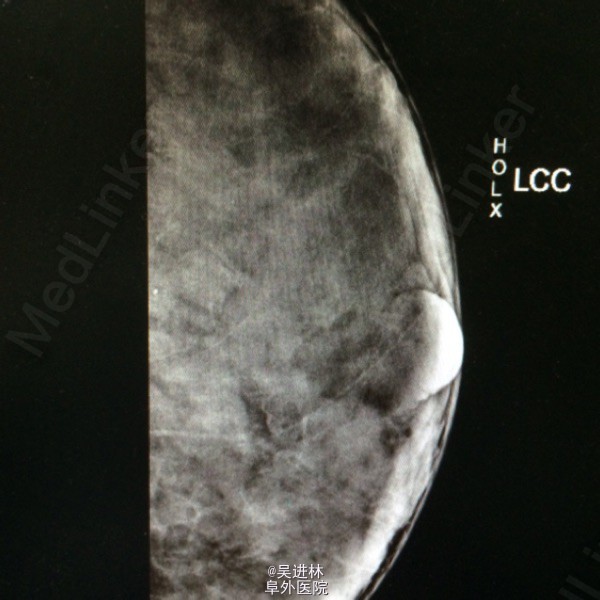

今天本来打算继续腹膜后脂肪肉瘤,但是悲闻姚贝娜因癌去世,遂借以下病例来谈谈乳腺癌钙化特点:患者中年女性,慢性起病,双侧乳房肿物4年余,以“双侧乳腺癌可疑”收入院。一般女性绝经候乳腺腺体开始萎缩,而此人腺体高度发达,脂肪组织几乎不可见,也是令人称奇(见钼靶)。查体双乳均可触及肿块,质硬,境界清,无压痛,表面欠光滑。腋下淋巴结未触及。钼靶显示双侧均可见簇状钙化。术前几乎被当作双侧乳腺癌来教学查房了一番,术后病理提示乳腺腺病。